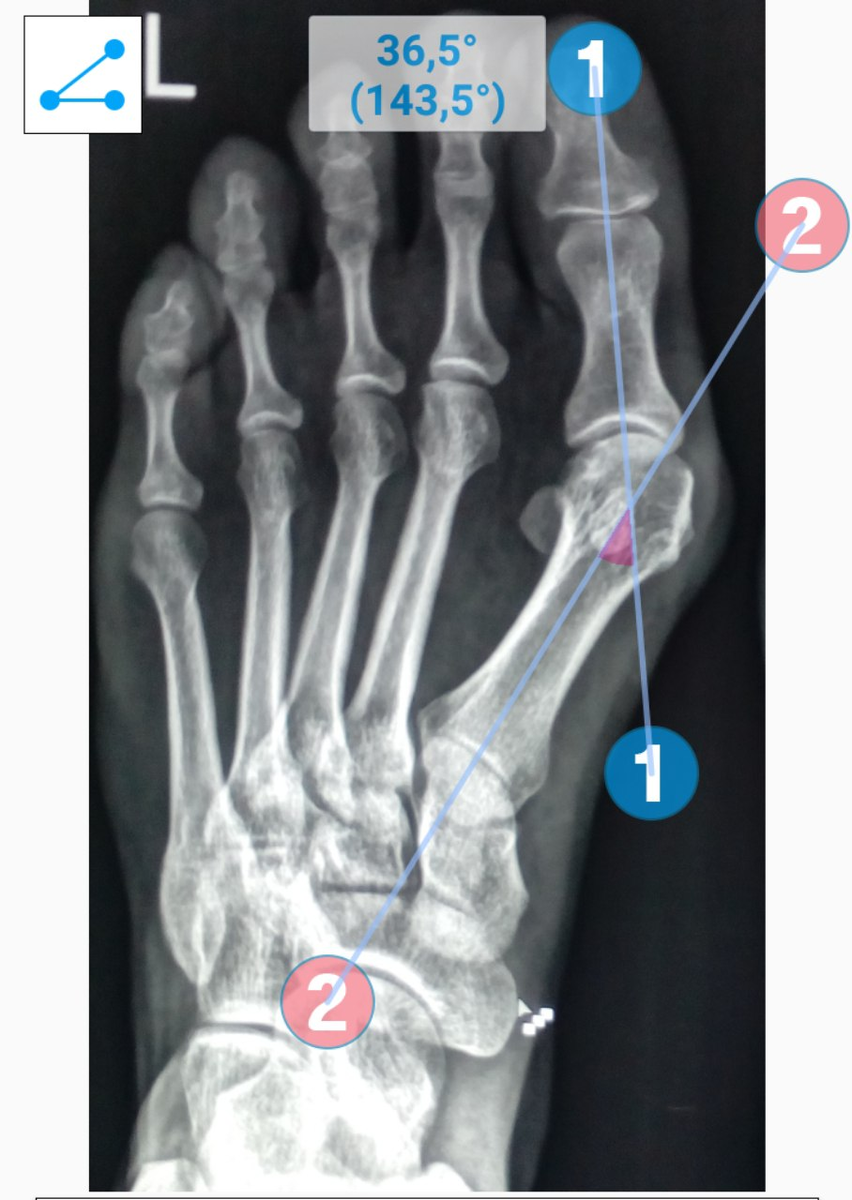

Если посмотреть на рентген, становится наглядно видно разницу.

В норме угол между первой и второй плюсневыми костями составляет 6–10 градусов. При hallux valgus он увеличивается, например до 18 градусов и более.

В результате такого отклонения первой плюсневой кости большой палец неизбежно уходит кнаружи. Именно так формируется деформация.